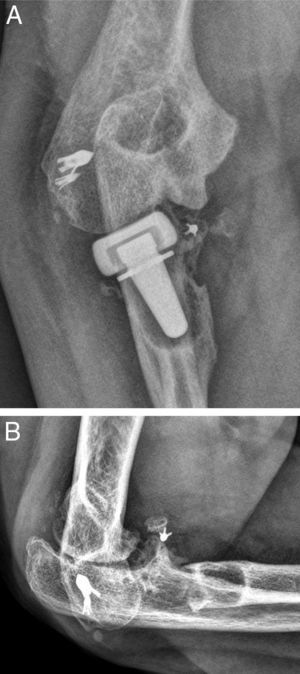

Up to 14 patients (32%) presented radiographic evidence of posttraumatic ulnohumeral arthritis which, in most cases, corresponded to grades I and II of the Broberg and Morrey classification. Only 1 patient presented severe radiographic changes due to posttraumatic arthritis (grade III). In total, 16 patients (37%) presented heterotopic ossifications. In most cases, these were located in the anterior region of the radio-capitellar joint, although in some patients they were located in the medial part of the elbow. These ossifications did not restrict the range of motion. Only 1 of these ossification cases corresponded to grade IIA in the Hastings and Graham classification (Fig. 1), with functional limitation in flexion–extension.

Three of the 9 patients (33%) who presented complications required a new surgical intervention for the treatment of their lesions. In one case, the patient suffered a dislocation of the prosthesis in the immediate postoperative period, which was treated by replacing the implant with another of a smaller size. The other 2 cases corresponded to painful aseptic loosening, with radiolucency around the entire prosthetic stem, requiring revision surgery. One was a patient who had suffered a “terrible triad” and who developed pain symptoms in the radial side of the elbow, with periprosthetic osteolysis, heterotopic ossifications and severe ulnohumeral osteoarthritis (or arthrosis) 4 years after the surgery (Fig. 3A and B). The patient was reintervened, with radial implant resection arthroplasty which led to the cessation of pain symptoms and a good functional result (Fig. 4A and B). The initial lesion in the other patient was an Essex-Lopresti fracture-dislocation which began with pain in the radial head, associated with signs of radiolucency around the prosthetic stem, 3 years after the initial surgery. The reoperation consisted of replacement with a new cemented prosthesis, leading to cessation of symptoms in the early postoperative period.